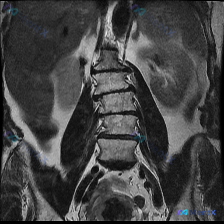

这个腰椎MRI提示“脊柱侧弯”?影像科医生却说“没见到明显侧弯”

- 输入指向:“脊柱侧弯”

- 提供的影像:腰椎MRI T2序列-冠状位

- 脊柱排列:腰椎序列基本连续,未见明显的侧弯畸形或明显的椎体滑脱;双侧髂嵴高度大致对称。

- 椎间盘:L4/L5及L5/S1椎间盘T2信号较上方减低,可见“黑盘”征,提示脱水、变性改变;其余节段髓核高信号区有不同程度缩小。

- 其他:椎体骨髓信号中等,未见明显骨质破坏或肿瘤样改变;硬膜囊及神经根袖套在该切面未见明显截断。

- 主观/输入指向的“脊柱侧弯”,与影像科“未见明显侧弯畸形”的描述存在直接冲突。